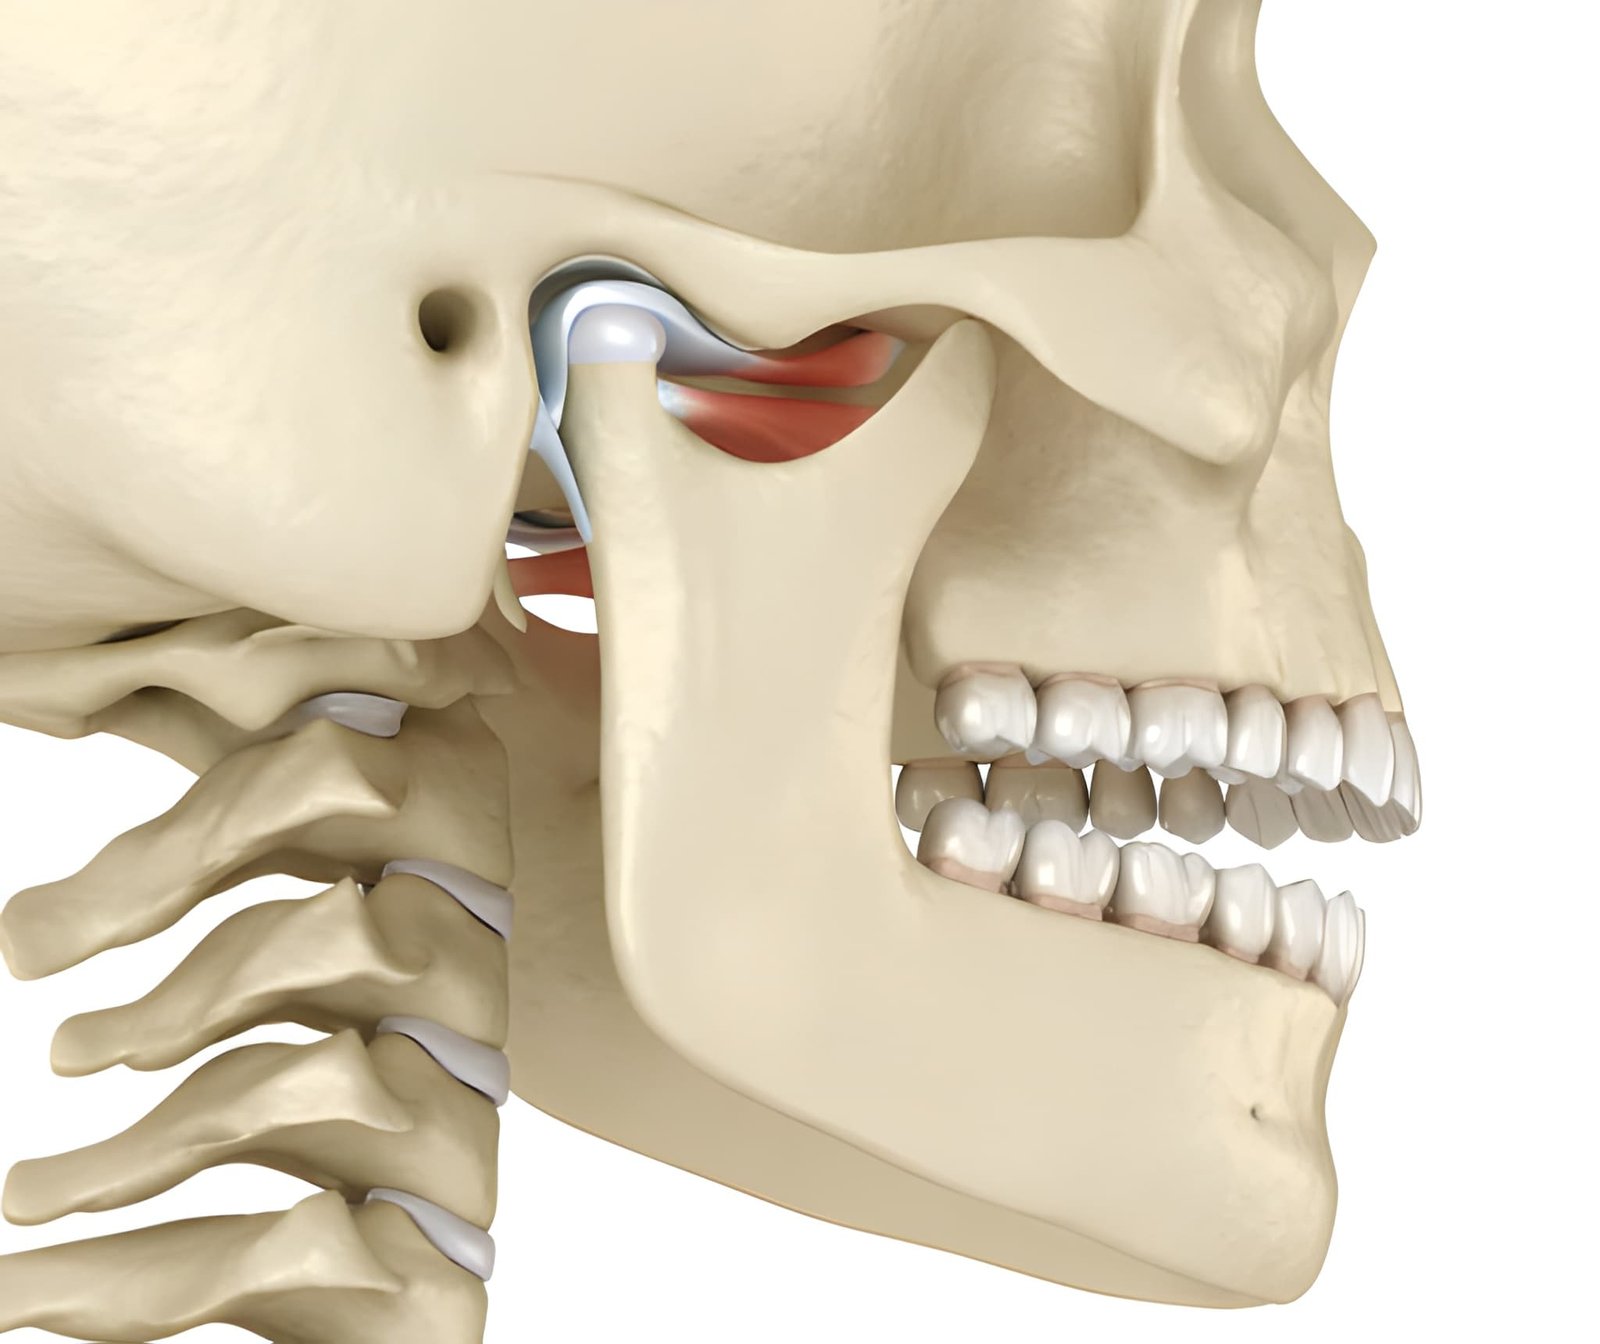

TMJ Pain Management

TMJ (Temporomandibular Joint) Pain Management focuses on diagnosing and treating discomfort in the jaw joint and surrounding muscles. TMJ disorders can cause jaw pain, clicking, difficulty in chewing, headaches, and facial discomfort.

Treatment begins with a thorough examination to identify the cause, which may include teeth grinding, misaligned bite, stress, or injury. Management may involve non-invasive therapies such as exercises, bite splints, medication, lifestyle changes, or advanced dental interventions to relieve pain and restore jaw function.